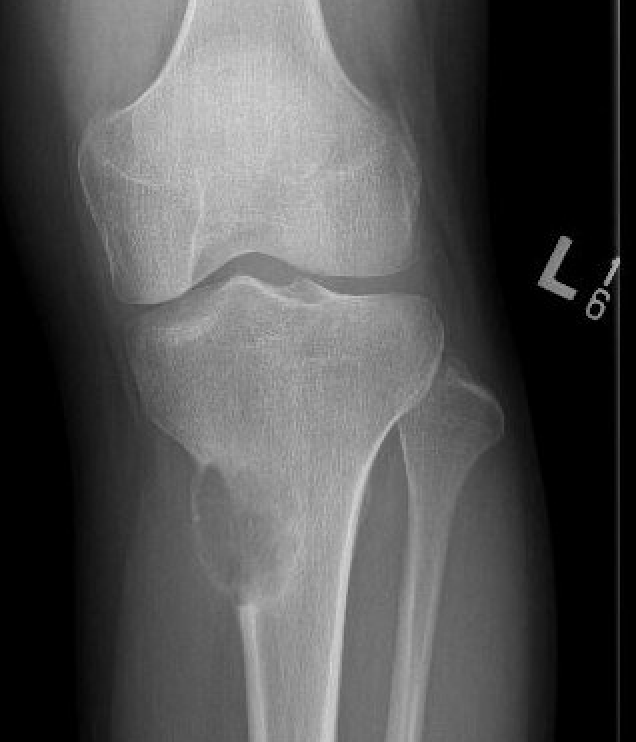

X-ray

Eccentrically located lucency in the metaphysis

- well-defined sclerotic margin

- local expansion but cortex intact